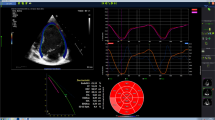

With conventional cardiac anatomy, as is often the case with cardiomyopathies, a number of steps in the workflow chain (e.g., plane localization for acquisition, volumetry post-processing, etc.) are relatively similar and repetitive across exams, yet time-consuming to manually perform. Automating (or nearly automating) such processes is now increasingly feasible through the use of AI/deep learning methods, which effectively can “learn” to execute rote tasks from prior data/examples. AI-based vendor solutions for automated ventricular contouring (with expert oversight when needed) are already available with promising results (Fig. 9) [51]. Other works-in-progress include using deep learning for automated cardiac cine scan plane prescription and selection of the optimal TI time for LGE imaging [52, 53]. These applications are likely to increase and to grow more robust in the coming years, allowing for more rapid cardiac MRI acquisition, post-processing and interpretation.

Automated ventricular contouring using deep learning in a 17-year-old boy with a normal cardiac MRI. Screen capture from a commercial cardiac post-processing software package employing deep learning techniques shows extremely accurate ventricular endocardial and epicardial contours (arrows) generated from a short-axis cine balanced steady-state free precession sequence prior to any human adjustment. LV left ventricle, RV right ventricle